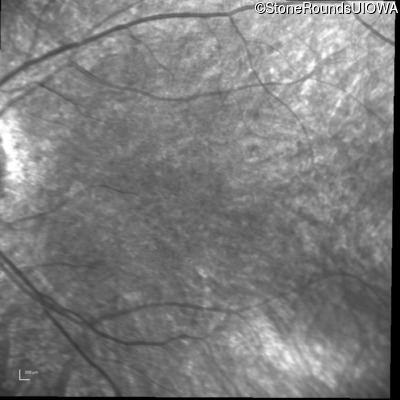

Infrared Fundus Photograph - Right - 20/80 -1

Exemplar

Infrared Fundus Photograph - Left - 20/80